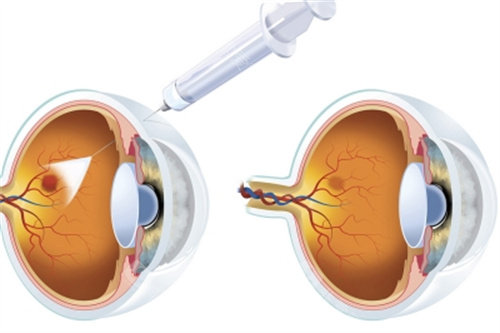

手术通常在局部或全身麻醉下进行,医生会在巩膜处制作微小切口,插入显微手术器械。

首可靠行玻璃体切除,清除眼内玻璃体以提供清晰视野;随后使用特定染色剂(如亮蓝)使黄斑前膜显色,便于比较准操作。

在显微镜下,医生用精细工具(如视网膜钩或镊子)小心抓住并剥离前膜,尽量减少对视网膜的损伤。

剥除后,详细检查视网膜表面是否有残留膜,并清理干净。然后,向眼内注入平衡盐溶液维持眼球形状,闭合切口。

术后,患者需使用抗生素和抵***症滴眼液预防感染,并定期复查以确保改善进程。